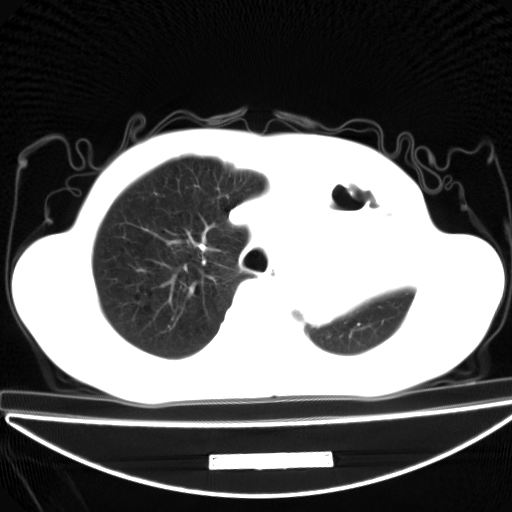

以下是引用杀毒软件在2009-4-28 17:58:00的发言:[br]考虑----左肺慢性肺脓肿形成继发上叶含气不良---抗炎后复查---待排肿瘤所致[br][br][本贴已被 杀毒软件 于 2009-4-28 18:01:26 修改过]